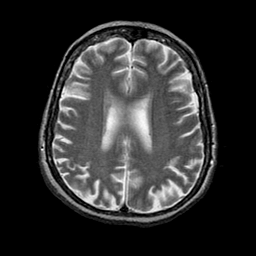

Alzheimer's disease: overlay -- Slice #16

[Home][Help][Clinical] Slice 16